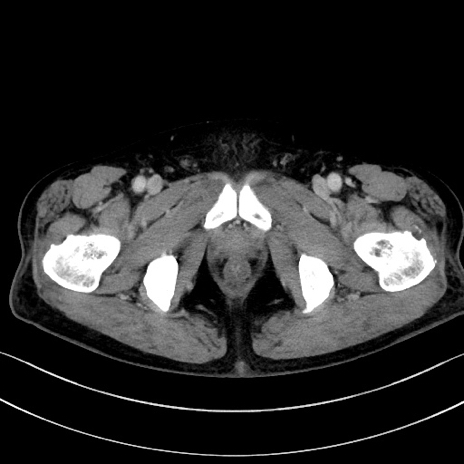

症例15(横断像)

【症例】70歳代男性

【主訴】腹痛

【現病歴】今朝から腹痛あり。全体的に痛い。特に左上の方。排ガスが今日はない。冷や汗が出る。

【既往歴】直腸癌術後

【身体所見】左側腹部〜上腹部に圧痛あり。腹膜刺激症状明らかなではない。軽度反跳痛。左下腹部に術後瘢痕あり。

【データ】WBC 7700、CRP 0.02